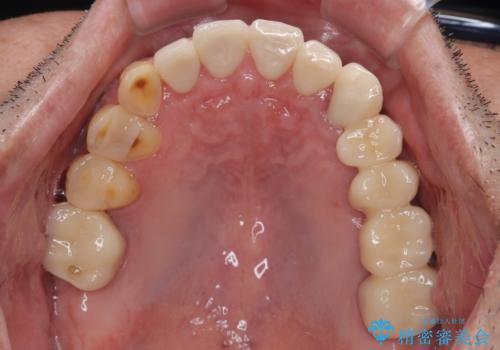

矯正治療は想定通り長期化しましたが、しっかりと奥歯の咬み合わせを向上させて前歯の被蓋を改善させることができました。

目立つ銀歯やすり減った前歯がセラミッククラウンとなり、患者様には大変満足していただけました。